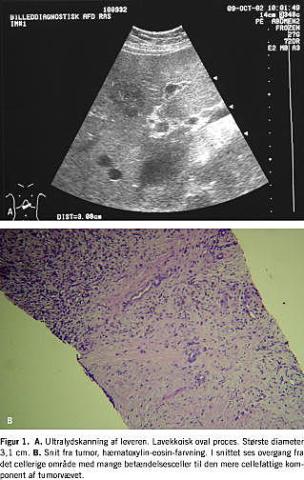

Ved klinisk undersøgelse blev der ikke fundet hepatomegali. Ved ultralydskanning af abdomen sås en ca. 3 cm stor lavekkoisk proces lateralt i venstre leverlap, som umiddelbart blev tolket som metastasesuspekt (Figur 1 ). Ductus choledochus fandtes antydningsvis ektatisk og målte 8 mm i diameter. Patienten blev herefter henvist til organkirurgisk afdeling til videre udredning.

Histologisk biopsi af leverprocessen viste levervæv med overgang til et mesenkymalt tumorvæv. Tumorvævet var i områder cellefattigt og hyaliniseret med få fibroblaster og myofibroblastlignende celler. I andre områder var tumorvævet cellerigt med talrige inflammatoriske celler i form af lymfocytter, plasmaceller og makrofager. En immunhistokemisk undersøgelse viste positiv reaktion for CD68 (makrofagmarkør) og vimentin (markør for mesenkymale celler), negativ reaktion for cytokeratin (bredspektret epitelmarkør) og C-kit (markør for bl.a. gastrointestinal stromatumorer). På baggrund af morfologi og immunohistokemi konkluderedes det, at det drejede sig om en myofibroplastisk inflammatorisk pseudotumor.

Ved ultralydskanning af abdomen ses IPL som en solitær homogen lavekkoisk læsion i leverparemkymet. Ved computertomografi ses kontrastopladning.